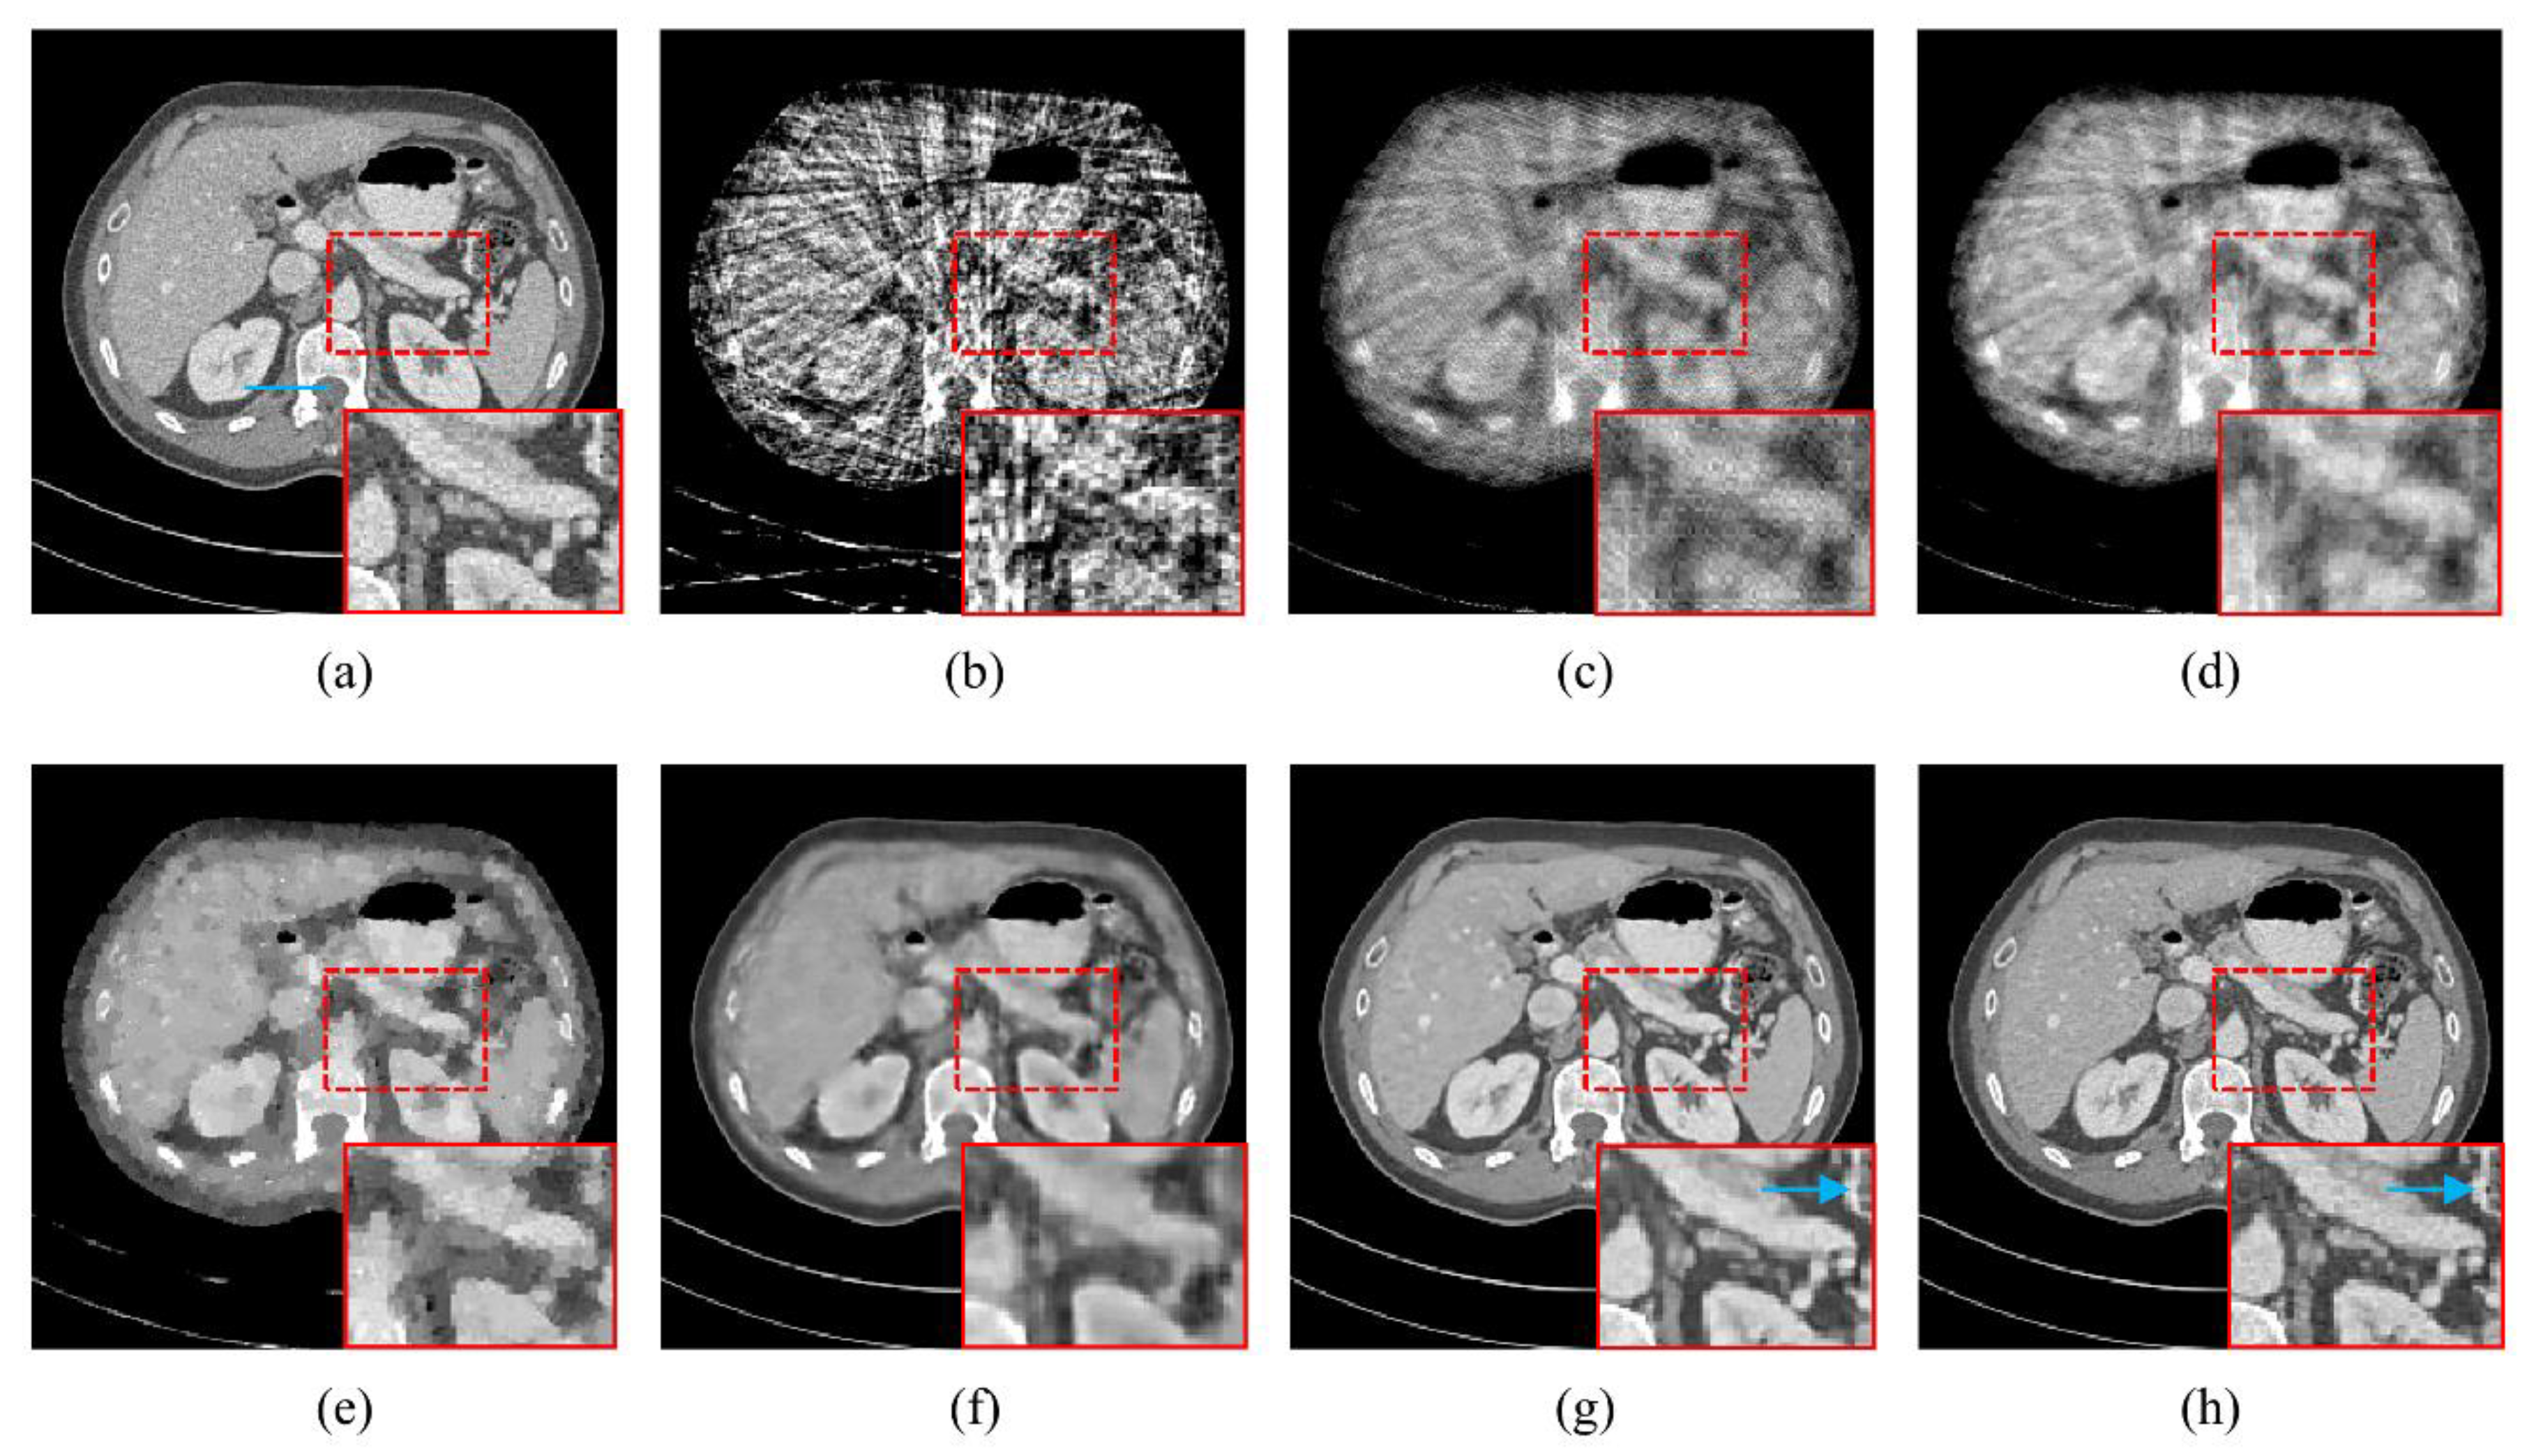

4.1. Visualization-Based Evaluation